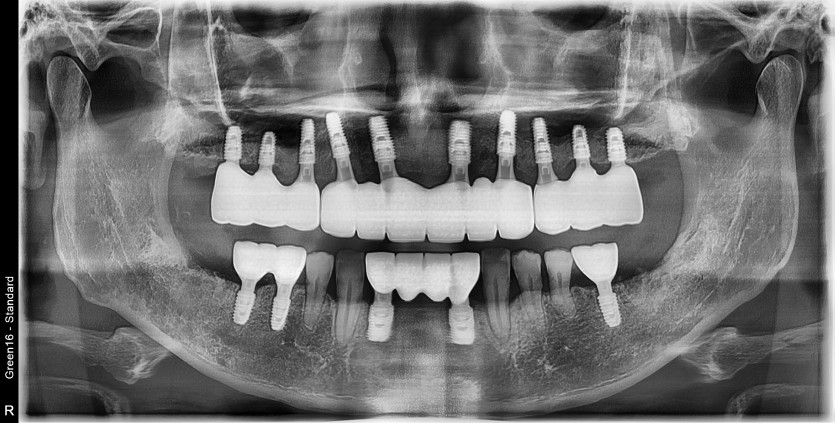

만 57세 전체 임플란트 증례입니다.(하악 일부)

15개의 임플란트로 완성하였습니다.